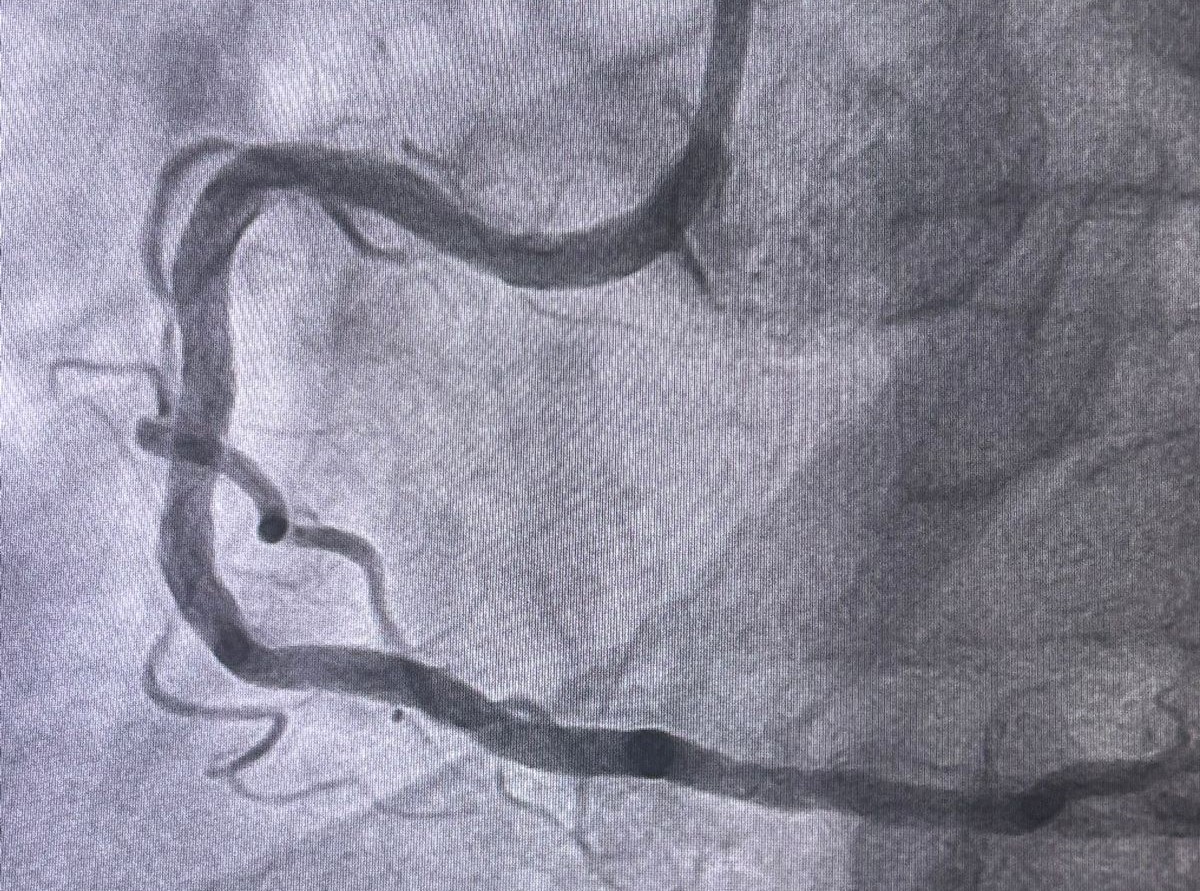

Realizado pelos cardiologistas intervencionistas Thiago Lisboa e Glauco Gusmão, o procedimento atendeu um paciente que apresentava dor torácica e falta de ar limitantes, com importante impacto na qualidade de vida. O cateterismo cardíaco evidenciou uma obstrução de 90% em uma artéria coronária, associada a uma placa extremamente calcificada (descrita como um verdadeiro “bloco de cálcio”, conforme evidenciado nas imagens do exame), cenário em que as técnicas convencionais de angioplastia apresentam maior limitação técnica. Após o procedimento realizado com sucesso, o paciente recebeu alta hospitalar em menos de 24 horas.